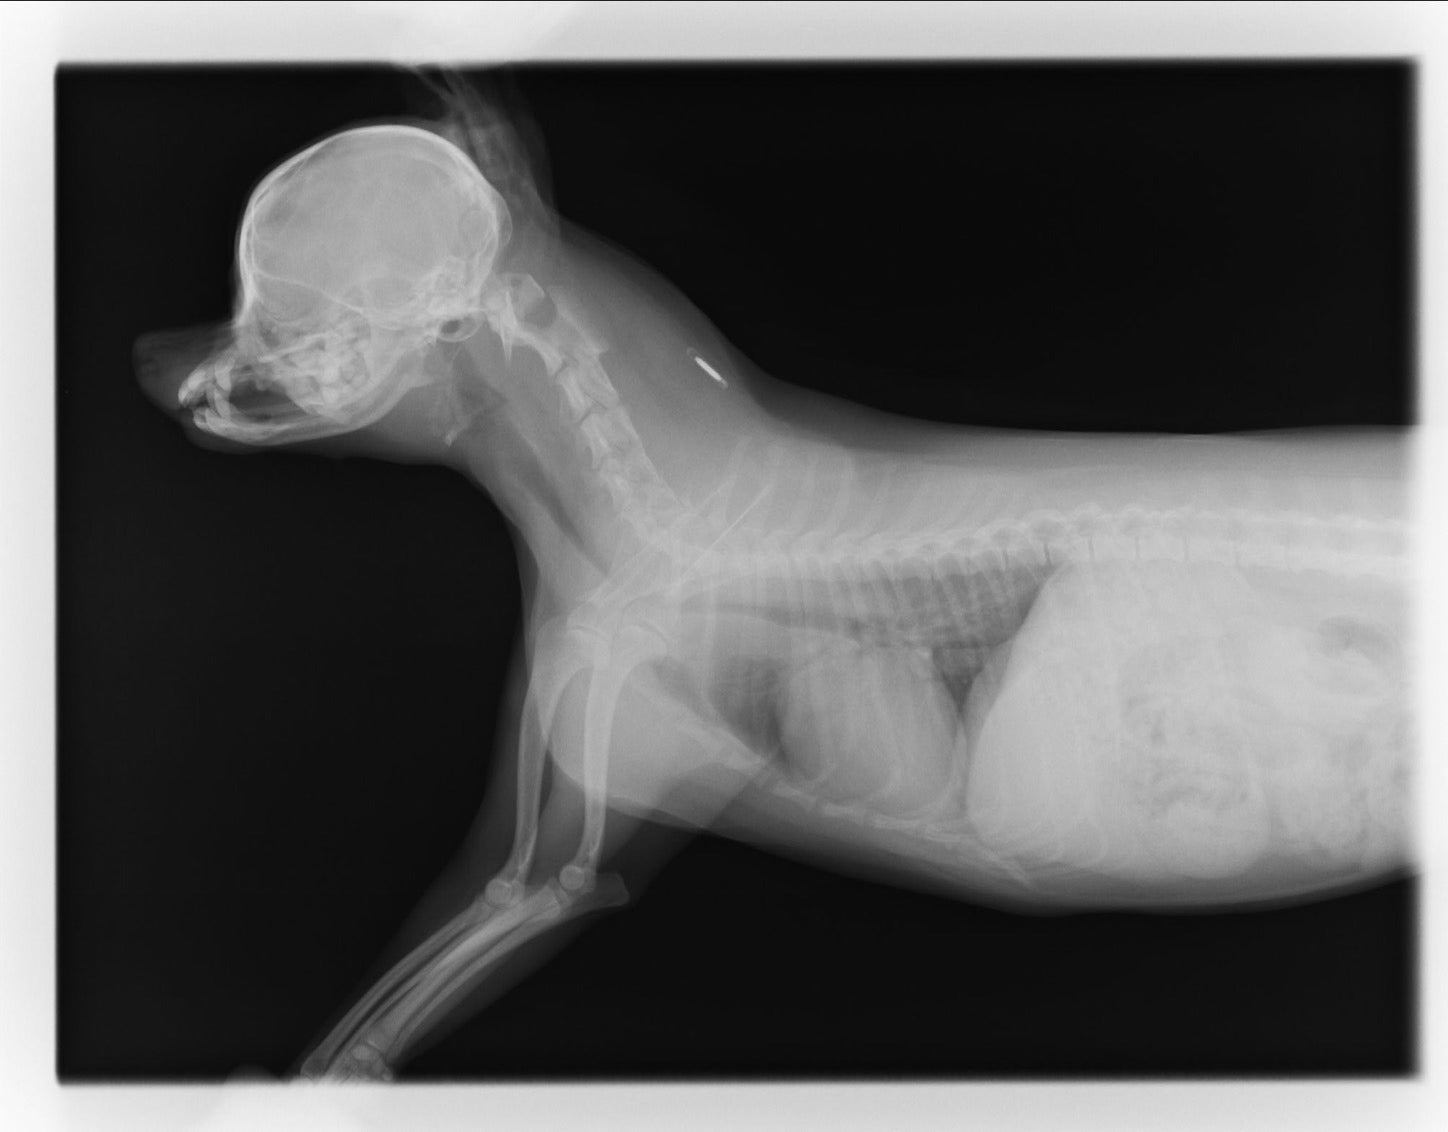

くーちゃんの病状は「グレード3.5」で、下の写真のとおり気道が潰れ、呼吸がうまくできない状況にあります。非常に苦しく、特に夜から明け方にかけて、ゼェゼェ‥と眠れない日も少なくありません。

気管虚脱は、気管の狭窄の度合により4段階に分類されます。一番症状の軽い「グレード1」では25%以下の気管の狭窄、最も進行している「グレード4」では75%以上の狭窄となります。

虚脱の初期病変は、90%以上が頚部気管で、進行するにしたがい胸部気管、さらには気管支へと潰れる範囲が広がっていきます。